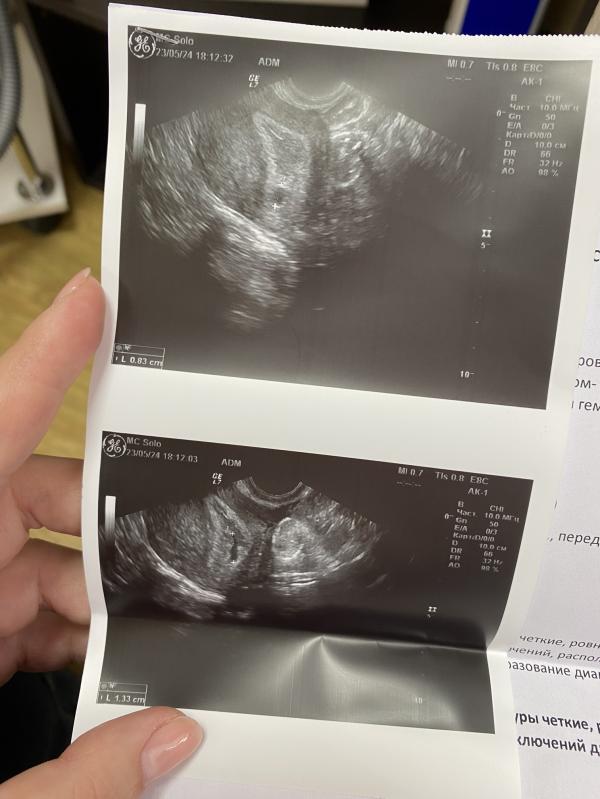

Ничего, замершая беременность. Эмбриона не появилось, все уменьшается, что расти должно. Отменять поддержку и ждать месячные.

Один раз замершая не является патологией, типо бывает у полностью здоровых. Вот если дальше еще раз, то уже обследование. Так что пока ничего страшного нет. Конечно очень обидно.